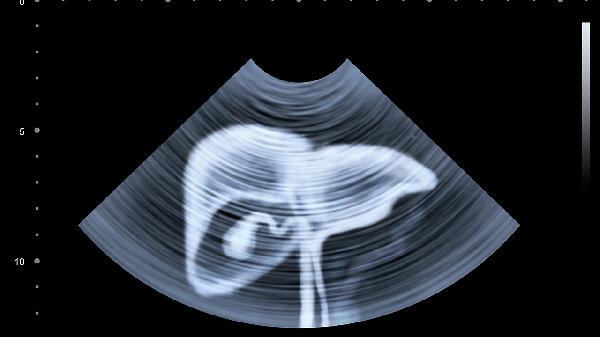

乙肝、丙肝感染者应每6个月做一次腹部超声联合甲胎蛋白检测。即使肝功能正常也不可掉以轻心,病毒DNA载量高者风险更大。